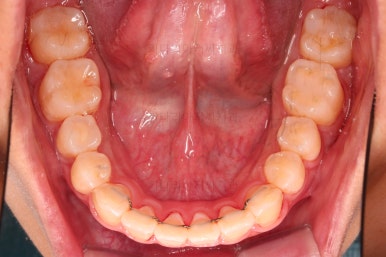

5. 마무리와 치료 종료

마무리가 잘 되었습니다.

큰 문제는 없었지만, 약간 삐뚤었던 치열이 가지런하게 정렬이 잘 되었고요.

맞물림도 매우 좋고, 뻗친 앞니 각도도 매우 좋아졌습니다.

입 안의 모습만 보면 최상급의 마무리가 되었고요.